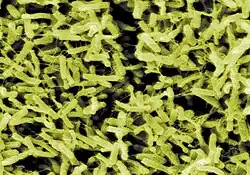

Elektronenmikroskopisches Bild von Clostridioides difficile | ||||||||||||

Clostridioides difficile (bis August 2016 Clostridium difficile) ist ein anaerobes, grampositives, endosporenbildendes Stäbchenbakterium der Gattung Clostridioides. C. difficile ist einer der häufigsten nosokomialen Erreger, sogenannter Krankenhauskeime.